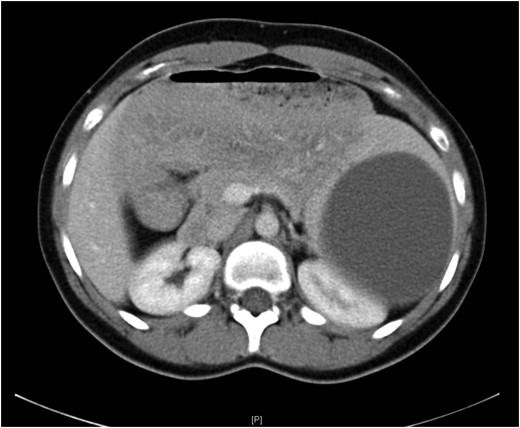

A 19-year-old female presented with a 2-day history of severe left upper abdominal pain. There was no known history of abdominal trauma or travel outside the UK. She was systemically well, had a soft abdomen with exquisite tenderness at the left upper quadrant and loin regions. The provisional blood tests, hydatid serology and chest and abdominal X-rays were unremarkable. An ultrasound scan showed a large splenic cyst with no increase in vascularity on Doppler assessment, while an intravenous contrast-enhanced CT scan showed a 12.5 × 9.7 × 10.7 cm well-defined cystic mass arising from the upper pole of the spleen (Fig. 1) with multiple fine echogenic shadows and medial displacement of the stomach and the left kidney (Fig. 2). Findings were consistent with the diagnosis of a simple splenic cyst. The patient was scheduled for an urgent laparoscopic de-capsulation, and received triple vaccination (meningococcal, pneumococcal and Haemophilus influenzae type B). Although 2 weeks are recommended between vaccination and splenectomy should this be needed, we proceeded to surgery after 10 days from vaccination as the patient was considerably troubled with abdominal pain and we were confident that a total splenectomy could be avoided.

Computed tomography showing medial displacement of the stomach and the left kidney by the cyst.